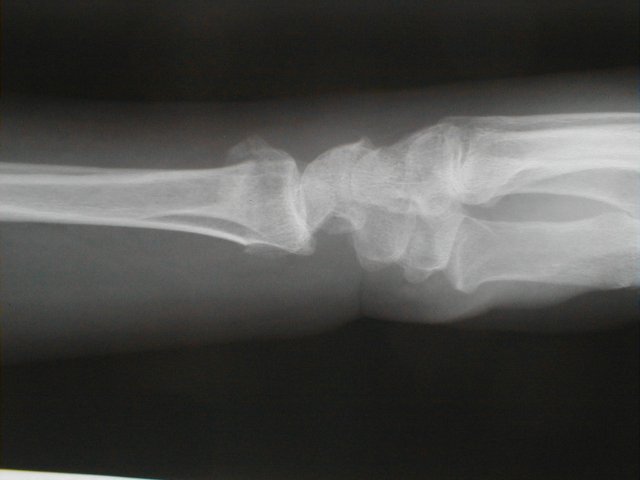

症例 9

左前腕骨骨折 コーレス骨折

72歳 女性

負傷原因   自宅近くを犬の散歩中足元が凍っていたために、すべり転倒した際手をつき負傷

整復操作

橈骨が背側に転位しているのが、若干気になるが高齢者でもあり整復操作は愛護的におこなった